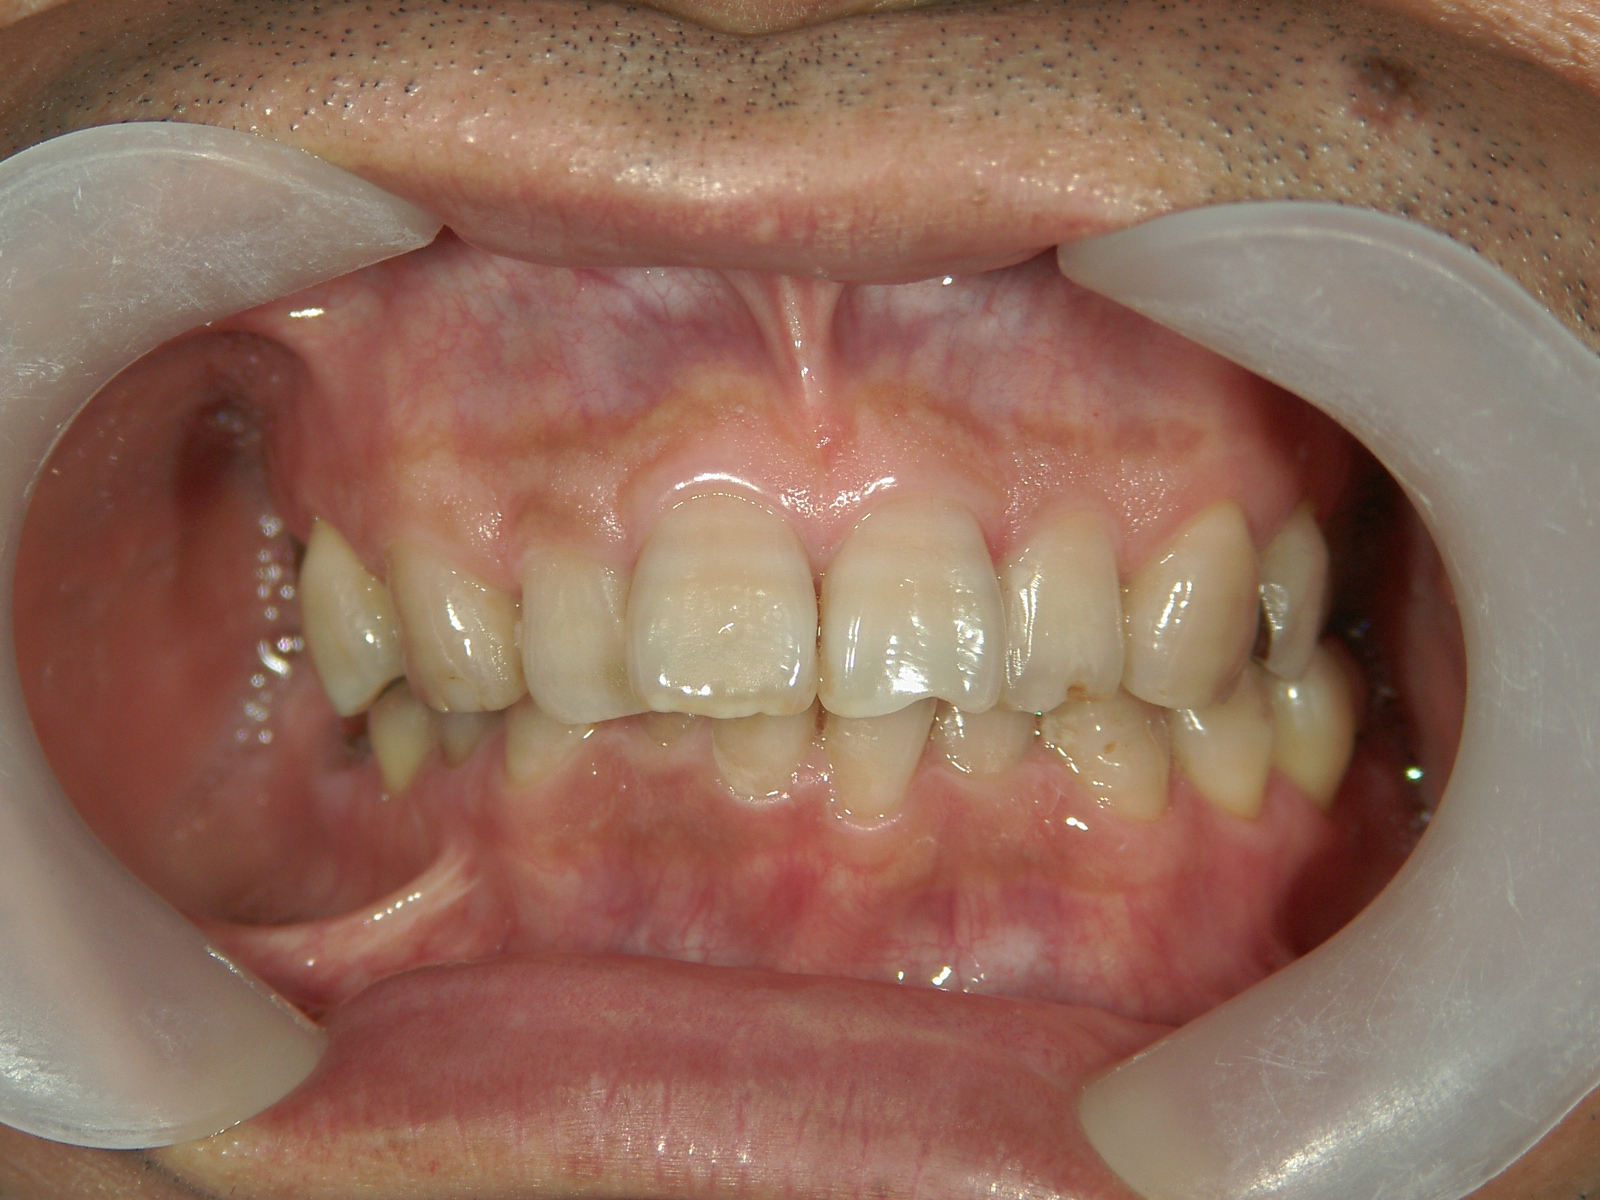

no.22_8175_治療前_右.jpgno.22_8175_治療前_正面.jpgno.22_8175_治療前_左.jpg

矯正歯科 治療後 左上6番欠損のため、7番を6番の位置へ前方牽引